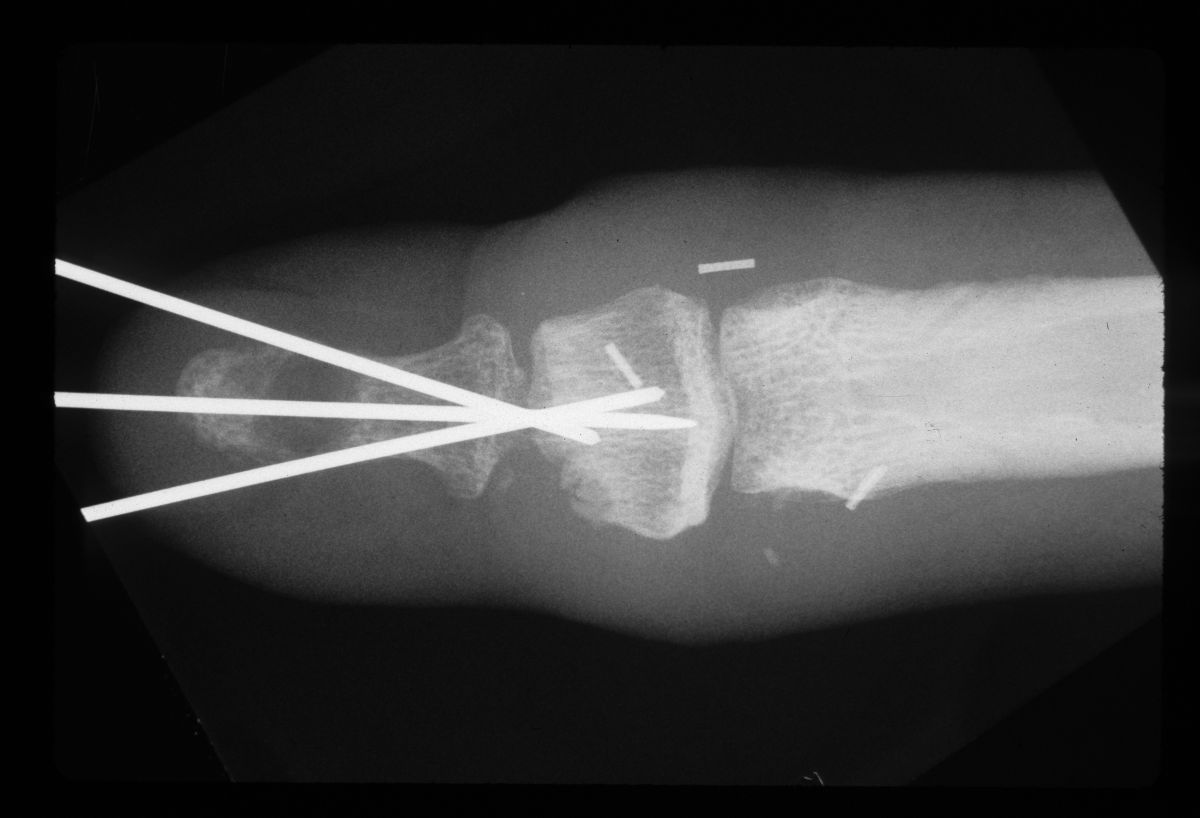

| Graft in place. Exposure facilitated by using 25 gauge needles to convert a Heiss to a Gelpi retractor. |

| Intraoperative films. |

| Temporary pin placement. |